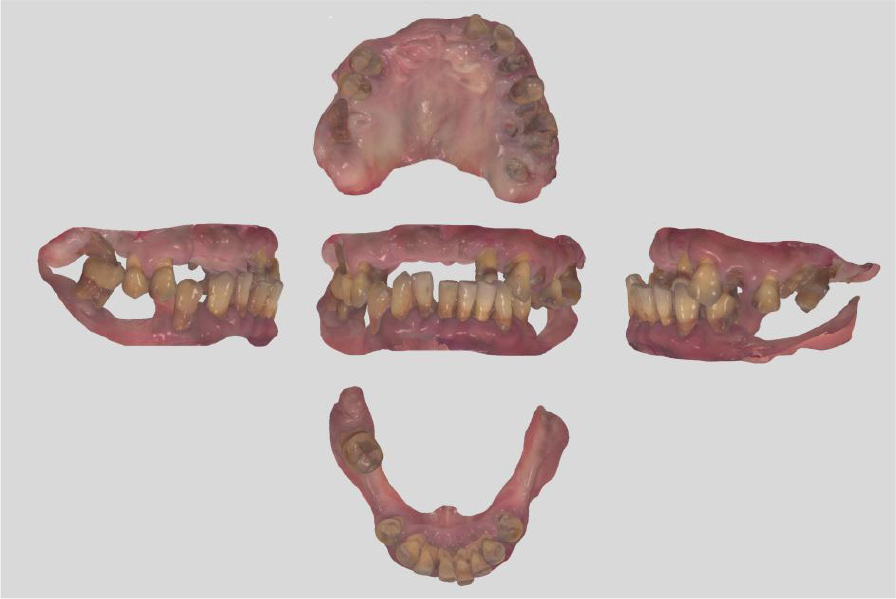

A 51-year-old male patient with no history of any serious disease visited a dentist with chief complaints of full-mouth implant treatment. Based on the initial clinical and radiographic examinations, the patient had severe periodontitis and was found to have multiple teeth with grade 3 mobility and heavy calculus deposition. In addition, many residual roots and teeth with advanced dental caries were observed (Fig. 1). A vertical stop was made in the left maxillary canine and left mandibular first premolar, and mastication was performed consistently on these teeth. No centric occlusion-centric relation (CO-CR) discrepancy was observed. The vertical dimension maintained by the left maxillary canine and left mandibular first premolar was judged to be satisfactory during the initial examination. In addition, full mouth scanning with an intraoral scanner (Trios 3; 3Shape, Copenhagen, Denmark) was conducted to use it as a reference point for the vertical dimension of the provisional prosthesis in future (Fig. 2).

To overcome the limitations of the mucosal-supported surgical guides in the edentulous area, all teeth, except two teeth for each of the upper and lower jaws, were extracted (Fig. 3). Next, implant surgical guides were designed by superimposing the intraoral scanning data on the remaining teeth as shown in the CBCT images. The diagnostic model was designed by duplicating the initial vertical dimension by superimposing the upper and lower jaw scanning data obtained after extraction from the initial scanning data. In addition, the position of implantation was planned according to the simulated design (Figs. 4 and 5) using the implant planning software (Implant Studio; 3Shape). Subsequently, the second step of the implant surgical guide was designed after virtually extracting the remaining teeth from the scanned data, considering the location of the implants to be placed at the extraction site (Fig. 6). Finally, provisional dentures were designed to maintain the initial vertical dimension (Dental System; 3Shape) (Fig. 7).